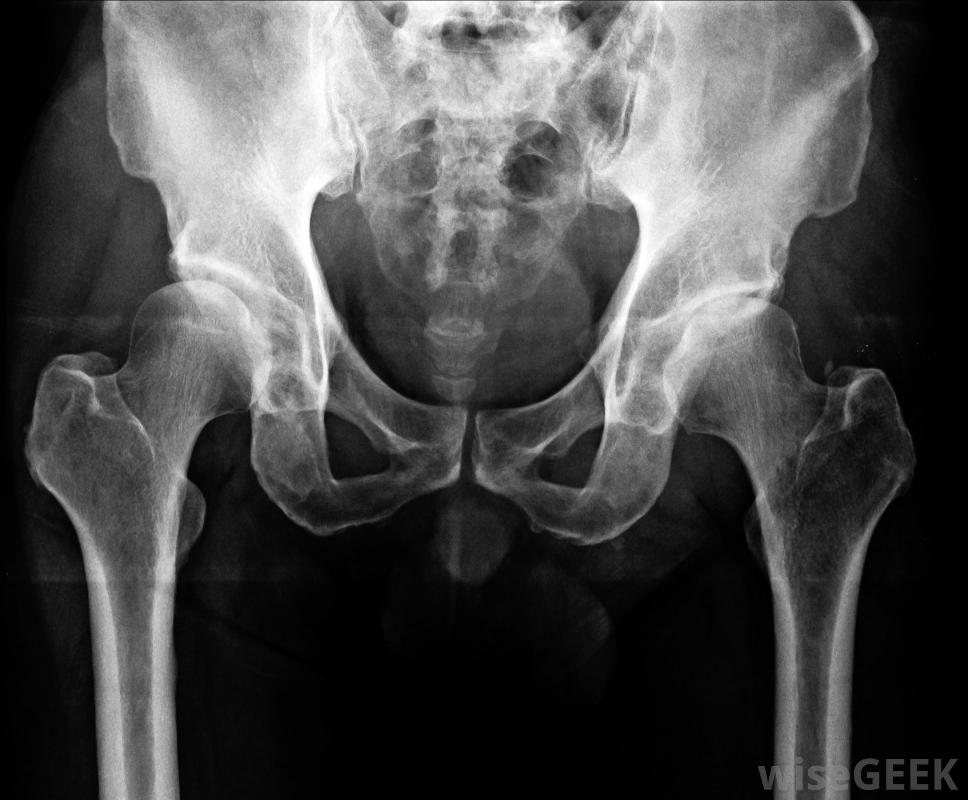

在實際注射之前,在局部麻醉前用碘和酒精混合物清洗髖關節,在透視或活體X光和對比染料的引導下,將小針插入關節區,用于避免神經損傷并確保針頭到達預期的關節區域。將集中劑量的消炎藥輸送到患處并拔出針頭。

X光可用于幫助髖關節注射。

在髖關節注射前,應將一根小針插入關節區域在X光的指引下。